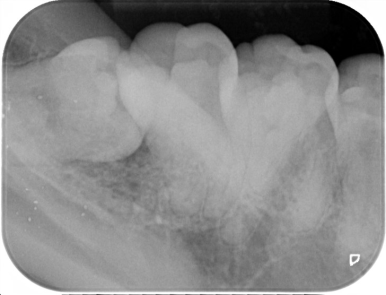

下の歯ですが親知らずに押されて、根と根がくっついています。

前の写真同様、根と根がくっつき、根の抵抗力を弱めます。

8.手前の歯の根を押す場合、押された歯の根は溶けてしまいます

一番左の親知らずが、大事な隣の歯の根を溶かしてしまいました。

下の親知らずが、前の歯の根を溶かしてしまいました。